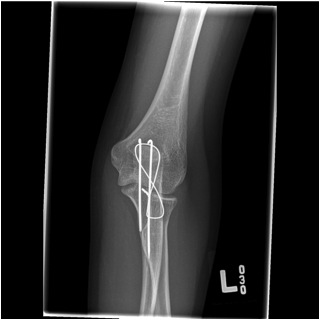

Tension band wire

Indication

Fracture proximal to center of rotation / midpoint of trochlea

Convert tensile distraction force of triceps into a compressive force

Issue

High rate of metal prominence / need for removal

Contra-indication

Fracture distal to center of rotation

Highly comminuted fractures

Oblique fractures

Technique

- fix with unicortical K wires

- drill hole in ulna distally

- pass 20 gauge wire and form figure of 8 wire about wires, can pass under triceps

- twist via 2 knots